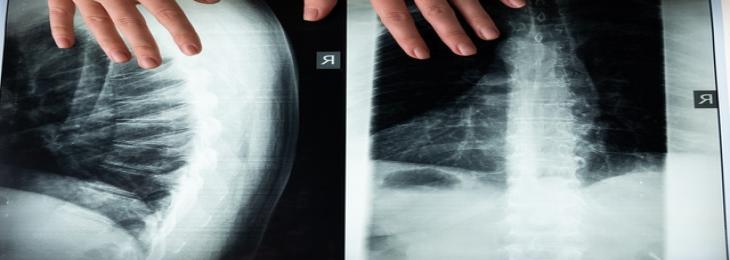

A study conducted by a team of researchers in the U.K. considered data from previous analyses and other studies to interpret the clinical effectiveness of common orthopedic procedur...

The smart pneumatic knee brace provides support to vulnerable knee joints and reduces chances of injury. To avoid any chances of i...